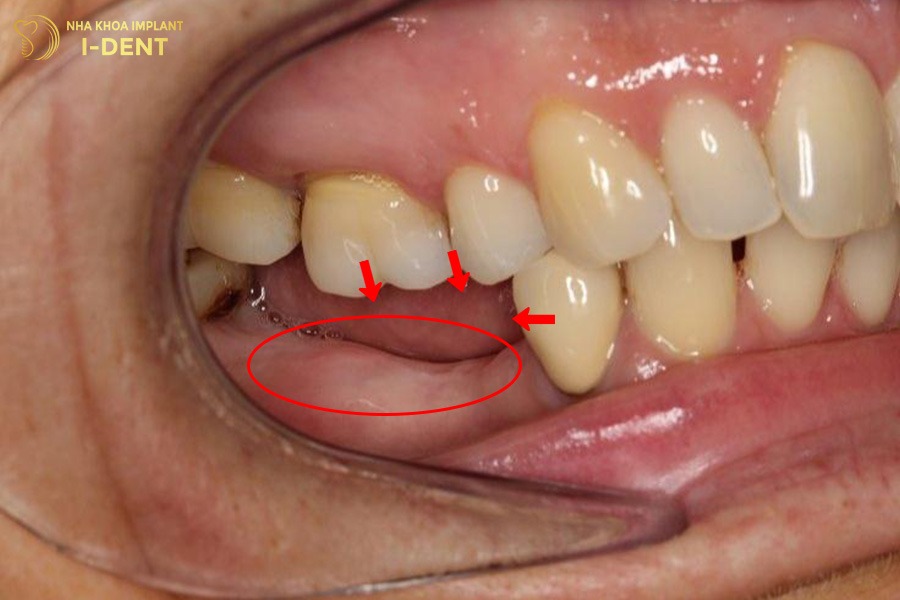

- Mất răng lâu ngày khiến các răng lân cận bị xô lệch, trồi răng hoặc đổ trục.

- Xương ổ răng tại vị trí mất răng bị tiêu biến làm giảm khả năng nâng đỡ răng.

Mất răng lâu năm khiến các răng lân cận bị xô lệch, trồi răng.